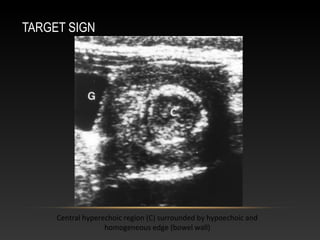

TARGET SIGN

Central hyperechoic region (C) surrounded by hypoechoic and

homogeneous edge (bowel wall)

-target sign (transverse)